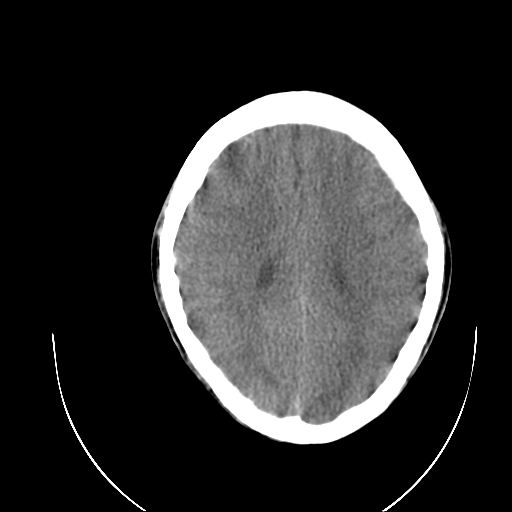

标题: PED1784:男,8岁,临床诊断:脑瘫。

02年做ct有脑水肿。

看见啥了?苍白球钙化?

苍白球钙化

8岁 苍白球钙化太早

1、侧脑室后角扩大,考虑胼胝体发育不良,建议mr

2、两侧苍白球钙化

8岁 苍白球钙化太早,建议查甲状旁腺功能。

基底节苍白球在14岁以后逐渐钙化,早于此前属于病理现象。

双侧苍白球见对称性钙斑。